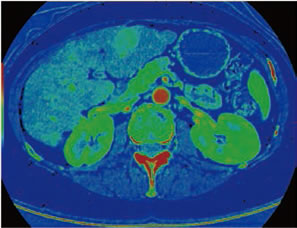

図6は肝ダイナミック撮影を行ったシングルエナジー画像とGSIXtream画像の比較である。

肝実質に注目するとGSI Xtreamでは特に均質な印象を受ける。また、デュアルエナジーとシングルエナジーで被ばくはほとんど変わらないということも注目すべき点である。

201710_voice_img_ct_01_08.jpg

図6: GSI Xtreamで撮影された臨床画像 2

このように、モノクロマティック画像によりヨードコントラストが増強され、かつS/N、アーチファクトには問題ない画質を、低被ばくで得ることができており、前述した「Single Energy CTでも得られる画像を一層効果的に応用すること」を、現実として享受できている。